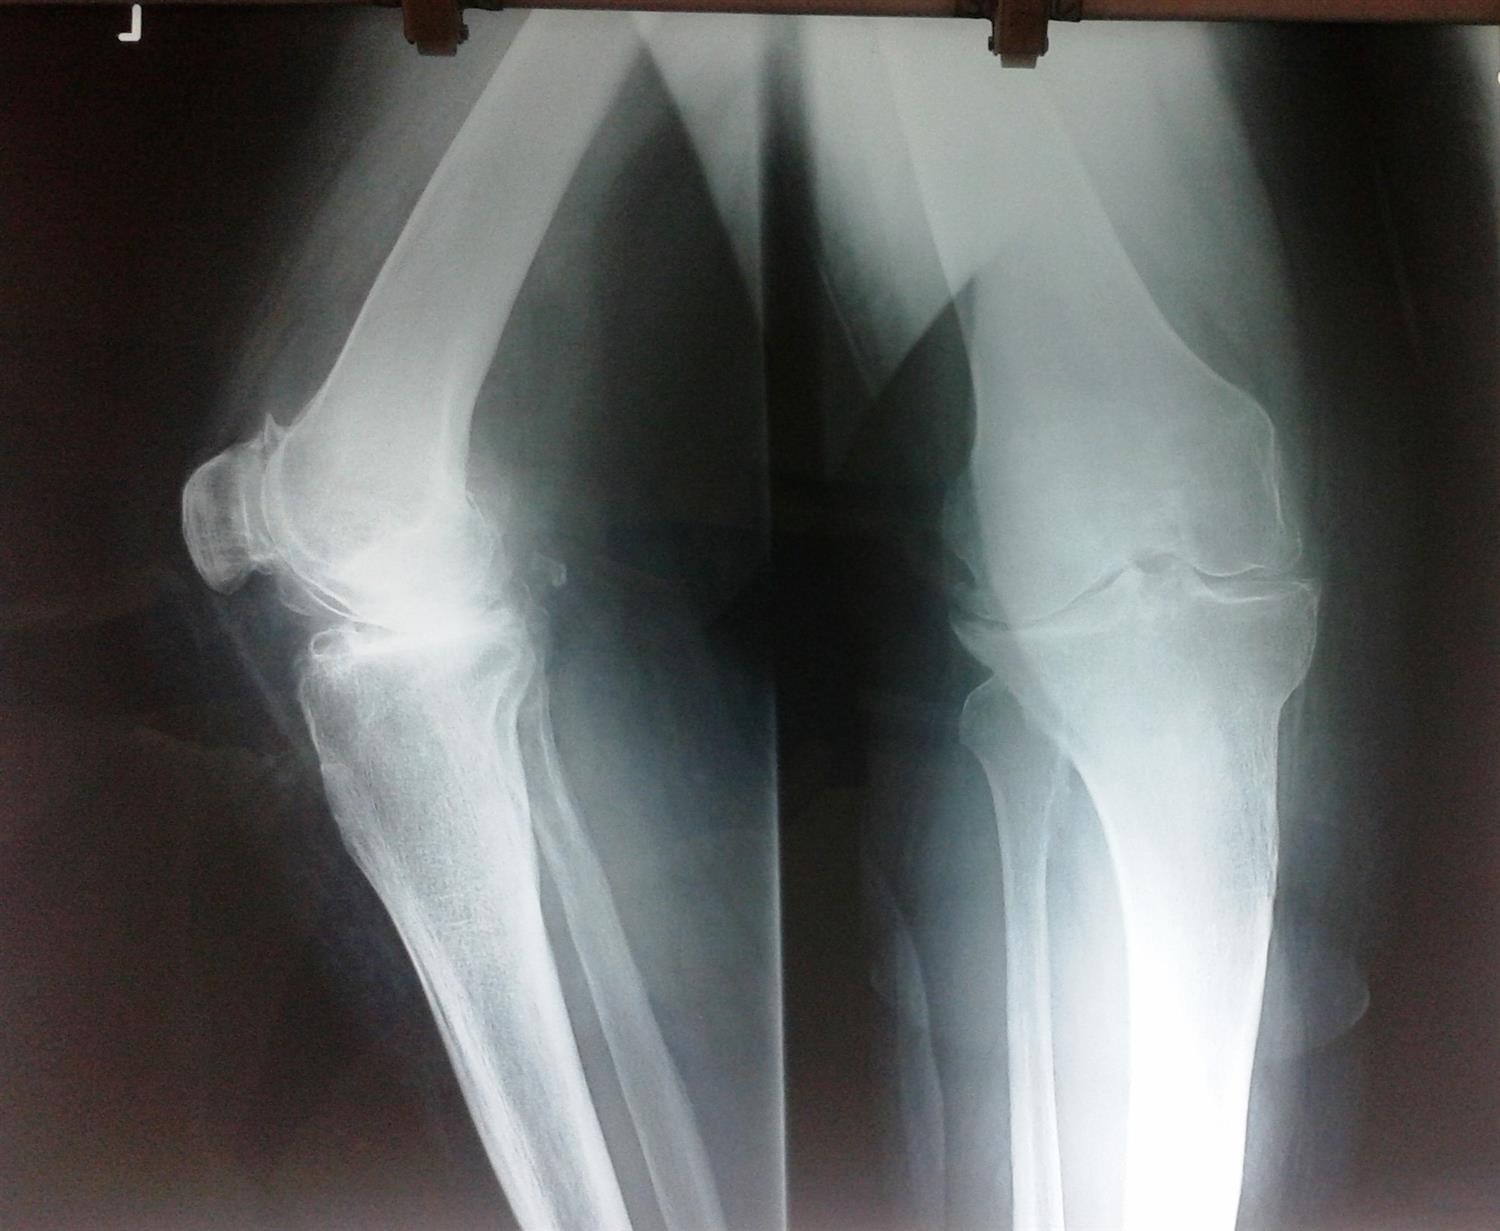

Knee Balancing Orthobullets . Measured resection is a total knee arthroplasty (tka) technique that relies on bony landmarks to set component placement and adapts the soft tissues to the chosen implant position. This article reviews different techniques to position tka implants, including kinematic alignment, which aims to restore the patient's. Soft tissue balancing during total knee arthroplasty (tka) is an important step for optimizing the outcome of the procedure and providing. Balance flexion and extension gaps by adjustment of polyethylene bearing thicknesss We compared knee arthroplasties performed using either a measured resection or gap balancing technique to determine if either operative.

Balance flexion and extension gaps by adjustment of polyethylene bearing thicknesss Soft tissue balancing during total knee arthroplasty (tka) is an important step for optimizing the outcome of the procedure and providing. This article reviews different techniques to position tka implants, including kinematic alignment, which aims to restore the patient's. We compared knee arthroplasties performed using either a measured resection or gap balancing technique to determine if either operative. Measured resection is a total knee arthroplasty (tka) technique that relies on bony landmarks to set component placement and adapts the soft tissues to the chosen implant position.

Knee Balancing Orthobullets Measured resection is a total knee arthroplasty (tka) technique that relies on bony landmarks to set component placement and adapts the soft tissues to the chosen implant position. Soft tissue balancing during total knee arthroplasty (tka) is an important step for optimizing the outcome of the procedure and providing. This article reviews different techniques to position tka implants, including kinematic alignment, which aims to restore the patient's. We compared knee arthroplasties performed using either a measured resection or gap balancing technique to determine if either operative. Balance flexion and extension gaps by adjustment of polyethylene bearing thicknesss Measured resection is a total knee arthroplasty (tka) technique that relies on bony landmarks to set component placement and adapts the soft tissues to the chosen implant position.